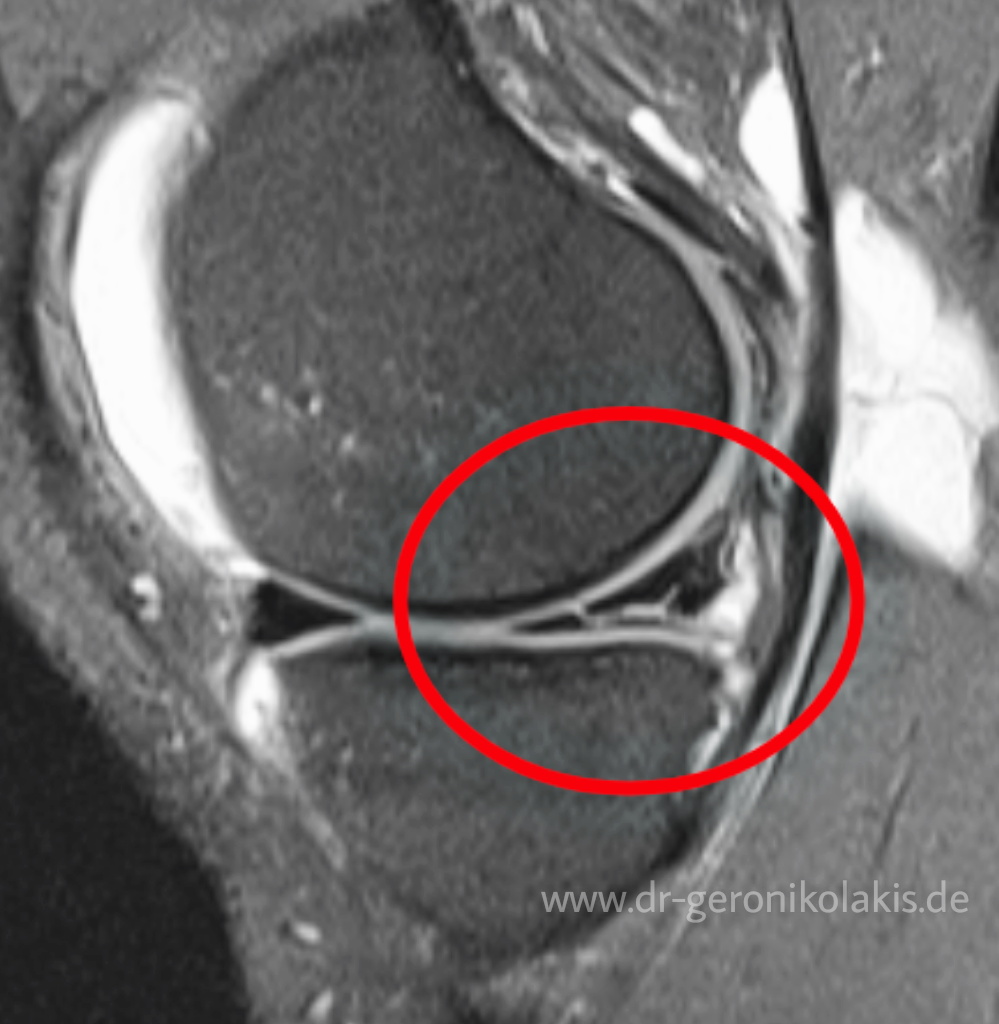

Source: mlgumcufv.pages.dev Meniskusriss Dr. Geronikolakis Facharzt für Orthopädie und Unfallchirurgie, Sportmedizin , Manchmal tritt auch eine Schwellung auf, die mit der Zeit schlimmer werden kann Ist der Innenmeniskus gerissen, zeigen sich Symptome wie deutliche Schmerzen, Bewegungseinschränkungen und Gelenkblockierungen